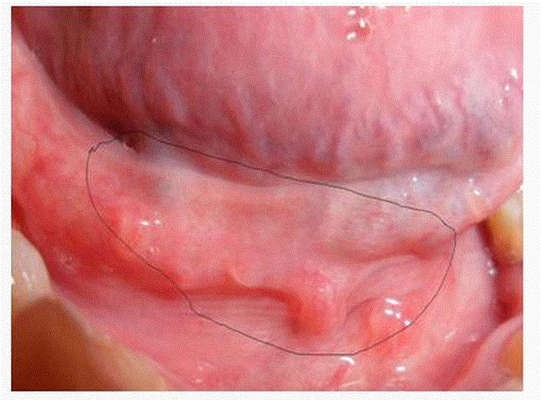

淋病圖片

淋病的症狀 (7)

淋病的症狀 (8)

淋病的症狀 (9)

淋病的症狀 (47)

淋病的症狀 (48)

淋病的症狀 (49)

淋病的症狀 (5)

淋病的症狀 (50)

淋病的症狀 (51)

淋病的症狀 (52)

淋病的症狀 (53)

淋病的症狀 (54)

淋病的症狀 (55)

淋病的症狀 (56)

淋病的症狀 (6)

淋病的症狀 (40)

淋病的症狀 (41)

淋病的症狀 (42)

淋病的症狀 (43)

淋病的症狀 (44)